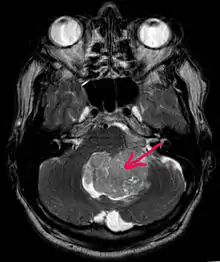

Магнитно-резонансная томография

В типичных случаях на МРТ эпендимомы видны в виде объёмных образований, которые заполняют, а иногда и полностью тампонируют полость IV желудочка и распространяются в большую затылочную цистерну или боковую цистерну моста. Солидная часть новообразования на Т1-взвешенных томограммах выглядит изо- или даже гипоинтенсивной и гиперинтенсивной на Т2-взвешенных томограммах[24].

Дифференциальная диагностика эпендимом с другими глиомами основывается в основном на их локализации и топографии, а не на различиях интенсивности сигнала или степени контрастного усиления[25]. Кистозный компонент имеет гипоинтенсивный сигнал на Т1-взвешенных МРТ и гиперинтенсивный по отношению к мозгу на изображениях, взвешенных по Т2. Гетерогенность структуры опухоли обусловлена наличием кист, петрификатов, опухолевой сосудистой сети. После введения контраста отмечается негомогенное усиление средней интенсивности[26]. Дифференциальную диагностику эпендимом боковых желудочков необходимо проводить с медуллобластомами и астроцитомами[23].

Анапластические эпендимомы отличаются более выраженной гетерогенностью сигнала, нечёткостью границ, большим распространением, интенсивным накоплением контраста и наличием зон некроза[24].